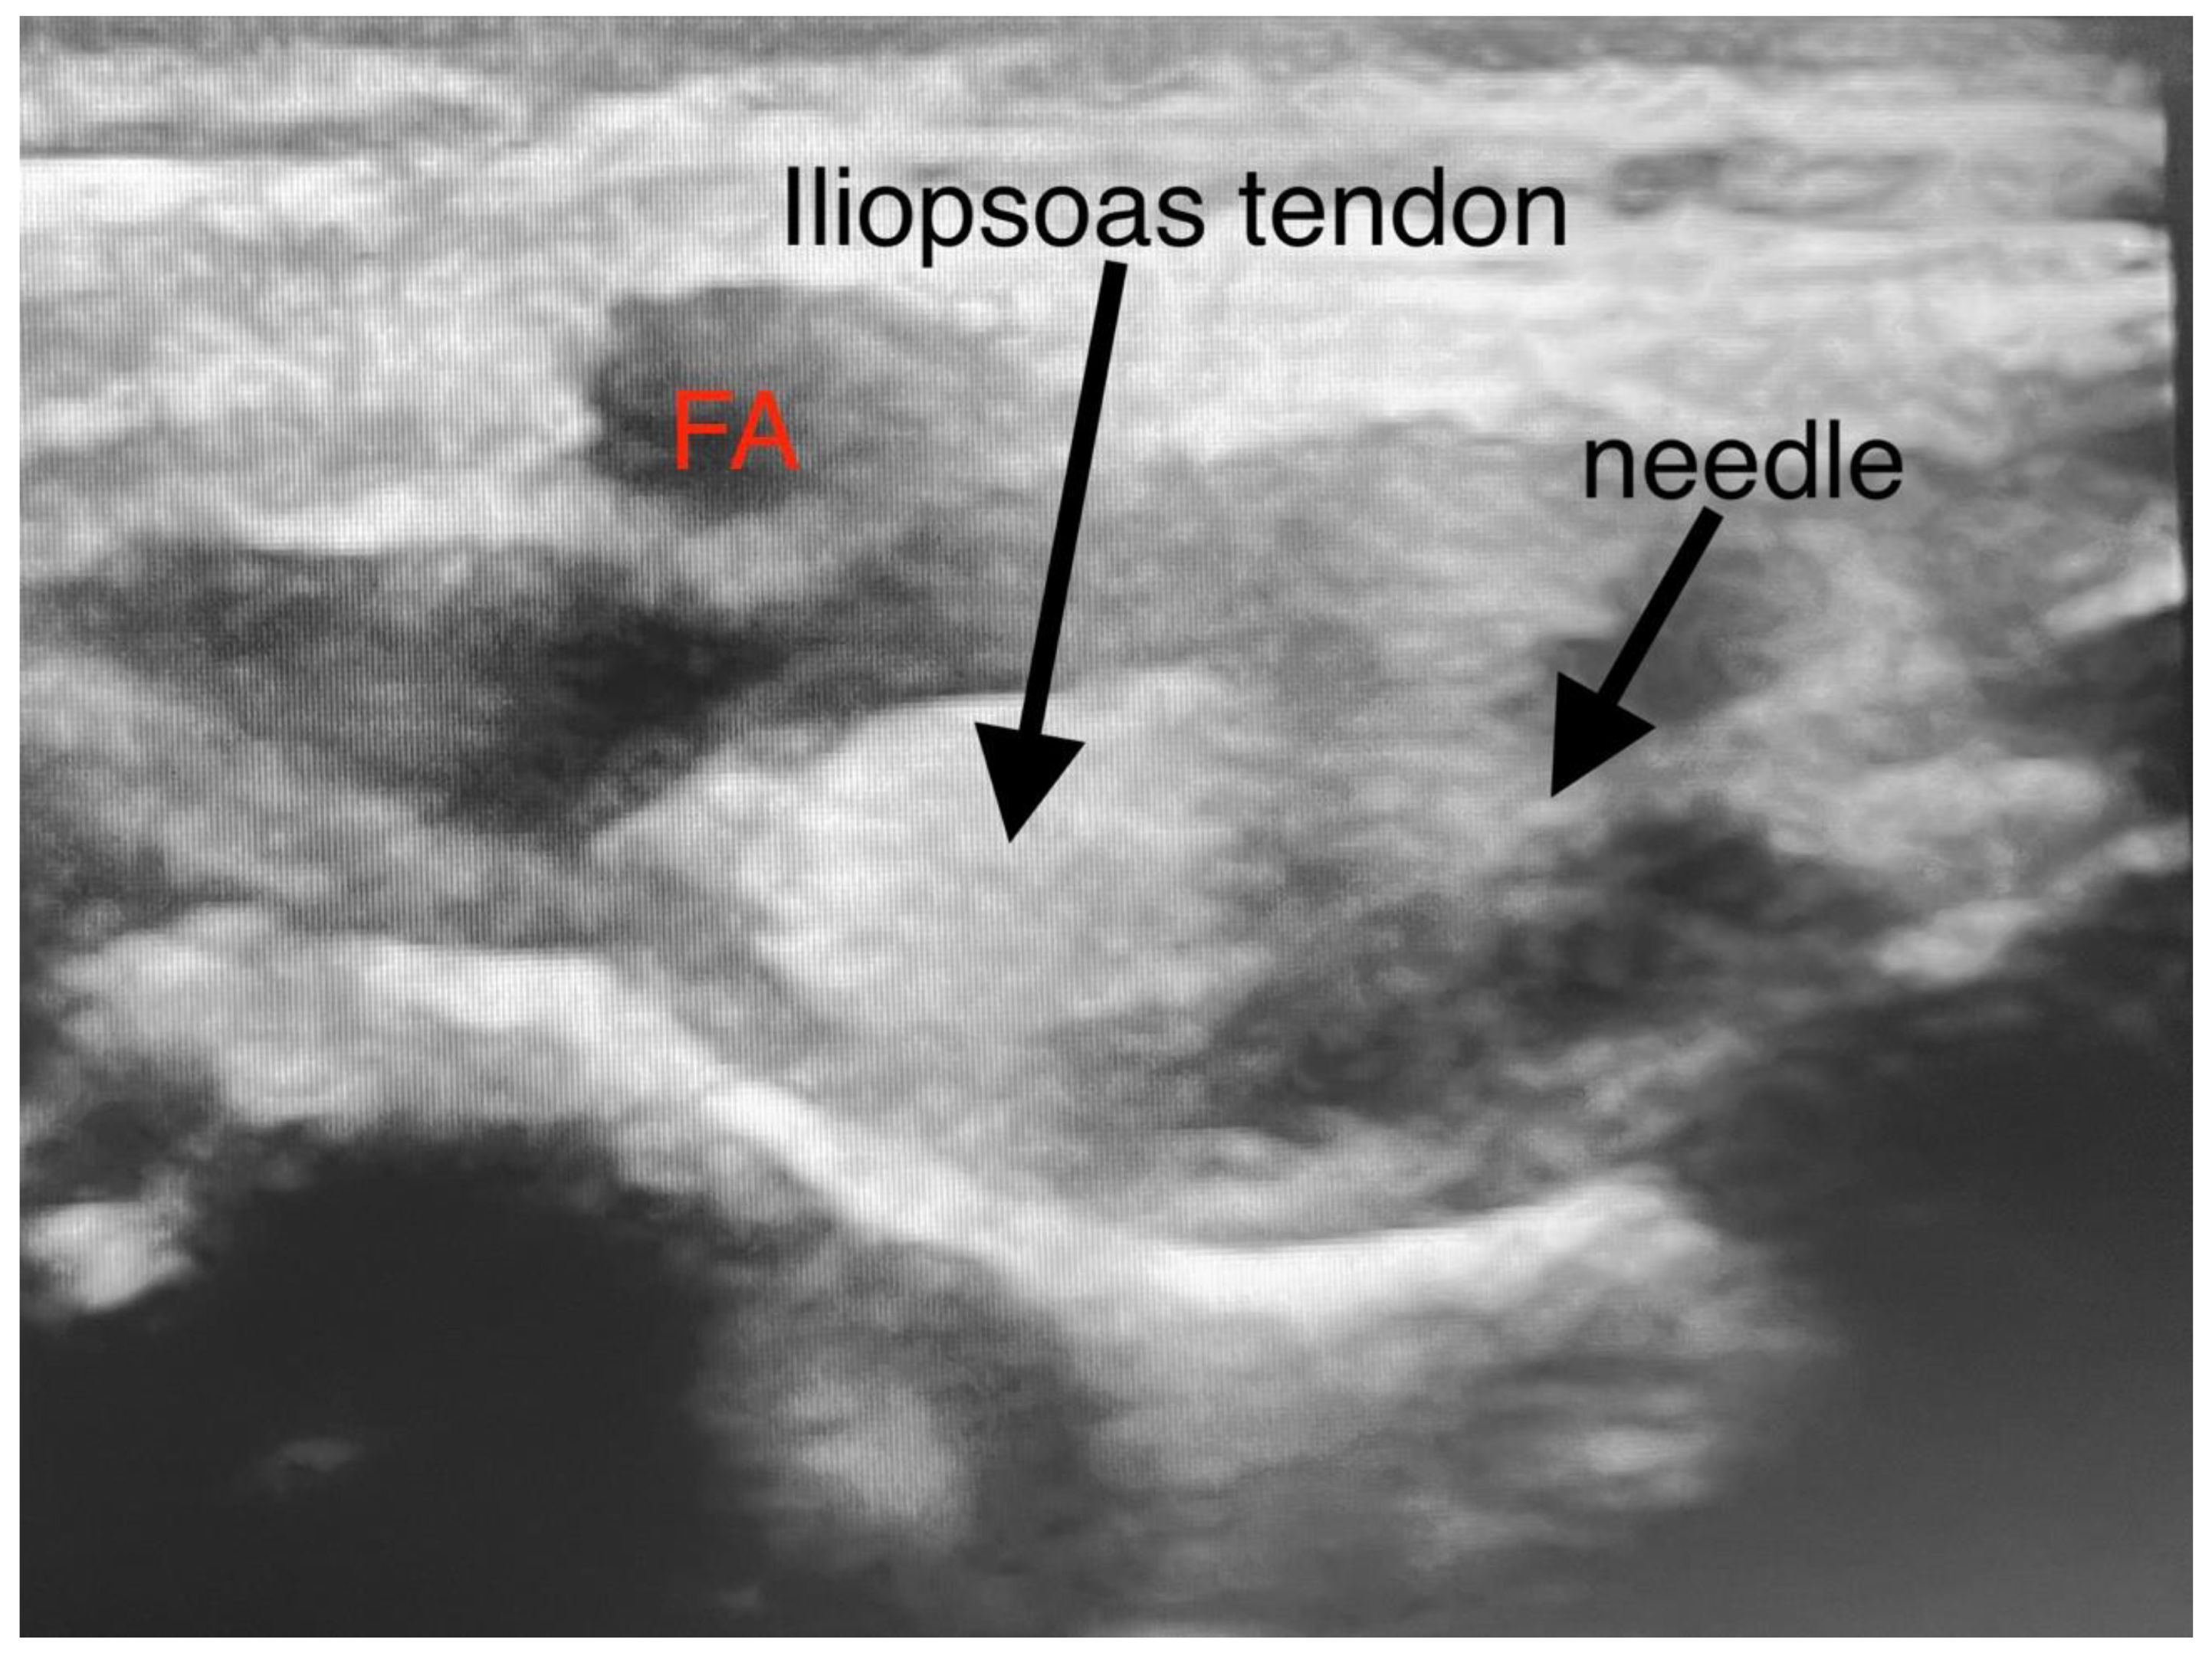

| Type and Volume of Local Anesthetic used for PENG block | 7,5mL of 0,2% ropivacaine | 5mL of 0,2% Ropivacaine |